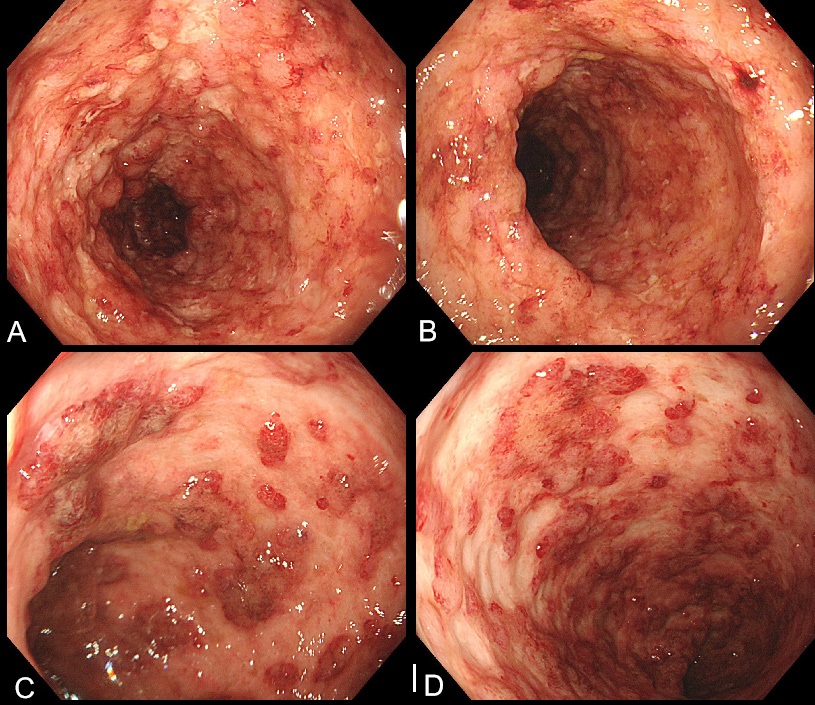

A 57-year-old man who was diagnosed with UC 3 years earlier was admitted to our hospital with abdominal pain and increased mucopurulent blood stool (more than 10 times/day) in August 2021. Laboratory tests showed increased Erythrocyte Sedimentation Rate (ESR, 23 mm/h)and low albumin (27.7 g/l). Autoantibody profile and a complete infectious workup turned out to be negative. Colonoscopy showed diffuse inflammation and ulcers in the left-sided colon (Figure 1). Chest Computed Tomography (CT) showed a small amount of pleural effusion, the initial consideration may be associated with hypoalbuminemia. We gived mesalazine 4 g/d and prednisone acetate (initial dose 35 mg/d), in addition considerd colonoscopy ulcer form cannot except with cytomegalovirus infection, empirical gived ganciclovir 250mg q12h. On 27 August and 8 September, He started induction therapy with infliximab 300 mg. Then the number of stools gradually decreased to 1-2 times / day.

Figure 1: Colonoscopy revealed mucosal diffuse congestion,oedema and scattered multiple irregular,deep chisel ulcers of the distal transverse colon, descending colon, sigmoid colon and rectum.The large mucosa of the sigmoid colon was absent and showed a mucosal island change. A: Descending colon; B and C: Sigmoid Colon; D: Rectum.